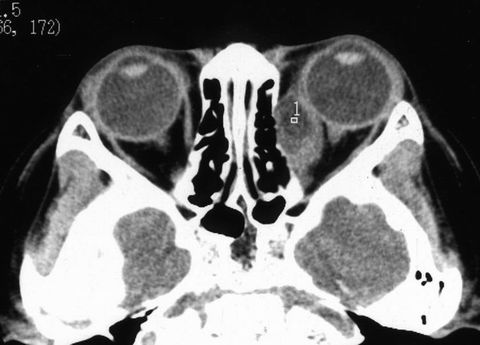

患者男性10岁。籍贯河南。 左眼球渐进性突出,间断红肿2年。曾用抗生素+激素治疗有效。但反复发作,眼球突出加重。于2000年5月住院治疗。入院检查:全身正常。眼科检查:双眼视力1.0。左眼眼睑无红肿,眼球突出测量:右眼12㎜,左眼18㎜,眶距95㎜。眶压增高,眼球突出,轻度外移位,内收明显受限,外展仅30°(图1)。眼底后极部轻度水肿。CT扫描如图2。入院期间左眼突然红肿,眼球突出加重,眶压增高,轻度恶心(图3)。